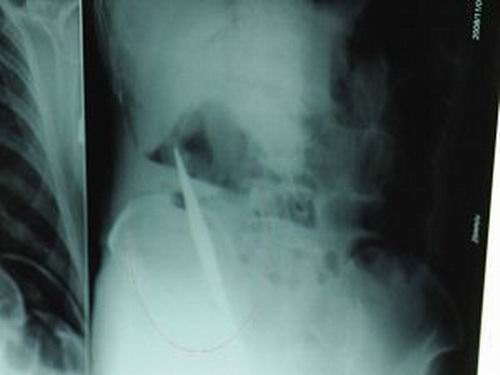

X光片上,尖刀清晰可見。

從男子體內(nèi)取出的尖刀足足有19厘米長。

江蘇銅山一58歲男子因服毒被送到醫(yī)院搶救,可醫(yī)生采取搶救措施后卻發(fā)現(xiàn)效果不佳。后來經(jīng)細(xì)致檢查,醫(yī)生有了個(gè)驚人的發(fā)現(xiàn),該男子的體內(nèi)竟然有一把尖刀,醫(yī)生通過手術(shù)將位于其腹部右側(cè)橫結(jié)腸下緣的尖刀取了出來。這把尖刀足足有19厘米長!據(jù)醫(yī)生推測,這把刀應(yīng)該是從肛門推進(jìn)體內(nèi)的,不知男子為何想以如此殘酷的方式結(jié)束自己生命。由于搶救及時(shí),該男子已暫時(shí)脫離危險(xiǎn)。

昨天(11月6日)上午,記者在徐州礦務(wù)集團(tuán)總醫(yī)院重癥監(jiān)護(hù)室見到了這名男子,目前他雖然已經(jīng)恢復(fù)了意識,但還不能開口說話,需要呼吸機(jī)輔助呼吸。據(jù)醫(yī)生介紹,4日中午12時(shí)左右,這名男子因服毒輕生被緊急送到醫(yī)院進(jìn)行搶救,之前,這名男子已經(jīng)在當(dāng)?shù)剜l(xiāng)鎮(zhèn)醫(yī)院進(jìn)行了近20小時(shí)的治療,但效果不佳!安∪吮晦D(zhuǎn)院到礦總院時(shí)已神志不清,血壓極低,處于休克狀態(tài)!本茸o(hù)人員給男子洗胃、初步處理以后,發(fā)現(xiàn)男子呼吸急促,于是趕緊給他拍片檢查。結(jié)果讓所有的醫(yī)生大吃一驚,竟有一把尖狀異物橫在該男子腹腔內(nèi)!當(dāng)天下午5時(shí)30分,輕生男子被推上了手術(shù)臺。經(jīng)過40多分鐘的手術(shù),該男子腹腔被打開,手術(shù)醫(yī)生發(fā)現(xiàn),男子體內(nèi)的金屬狀異物竟然是一把長19厘米的尖刀!